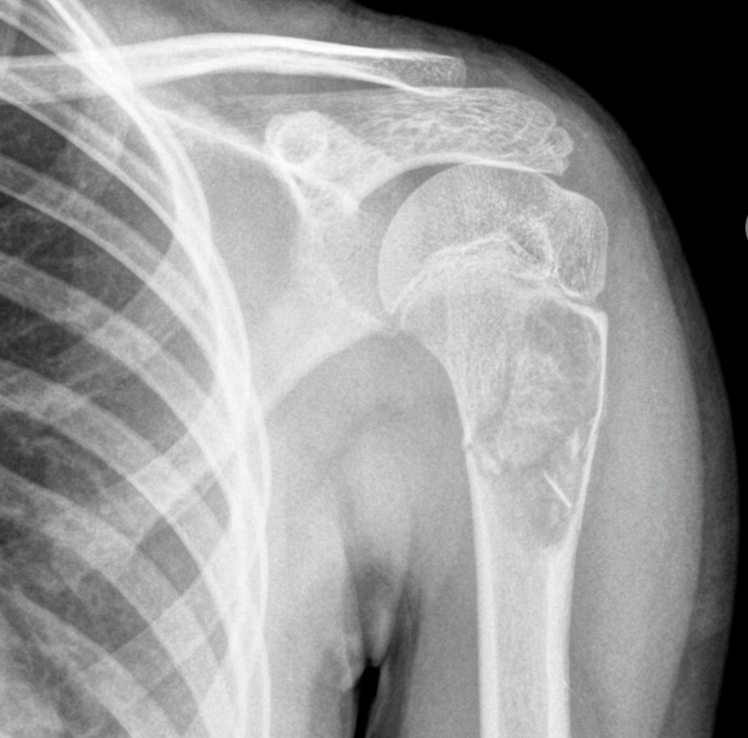

3. Unicameral bone cyst, pathological fracture, fallen fragment sign